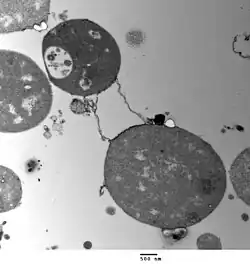

Una Forma L es una variante bacteriana carente de pared celular (PC) o con PC defectuosa. Se estudia por primera vez en Streptobacillus moniliformis, donde se observa que produce en forma espontánea una serie de variantes capaces de reproducirse en forma de pequeños elementos filtrables carentes de PC o con PC defectuosa.

Estos microorganismos reciben el nombre de Formas L (L: proviene de Lister Institute, Londres). Estas bacterias tienen una morfología colonial muy parecida a la de los Micoplasmas.

Las Formas L son el equivalente morfológico de los Protoplastos y Esferoplastos, aunque el término de Formas L se limita a los organismos capaces de multiplicarse. Algunas Formas L, si se elimina el agente inductor, pueden revertir a la forma original (variante transitoria). Otras son Formas L estables.